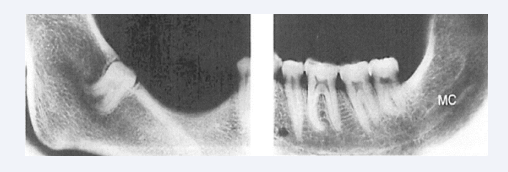

Absence of the mandibular canal

Absence of the entire mandibular canal or parts of the mandibular canal are morphologies seldom observed in mandibles with unilateral complete or partial agenesis of teeth [Figure 19] [27].

Figure 19 Radiographs of right and left sides in an anthropological mandible lacking mandibular canal in the right side. In the left side is the canal  present and indicated MC.

Figure 19: Radiographs of right and left sides in an anthropological mandible lacking mandibular canal in the right side. In the left side is the canal present and indicated MC.